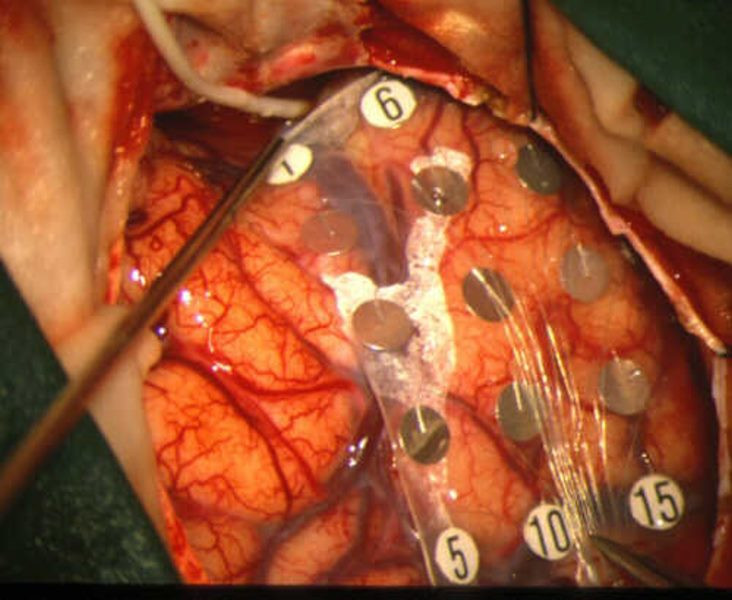

Cirugía contra la epilepsia

Envíado por Dr. Mauricio Ernesto Palacios Marchesini